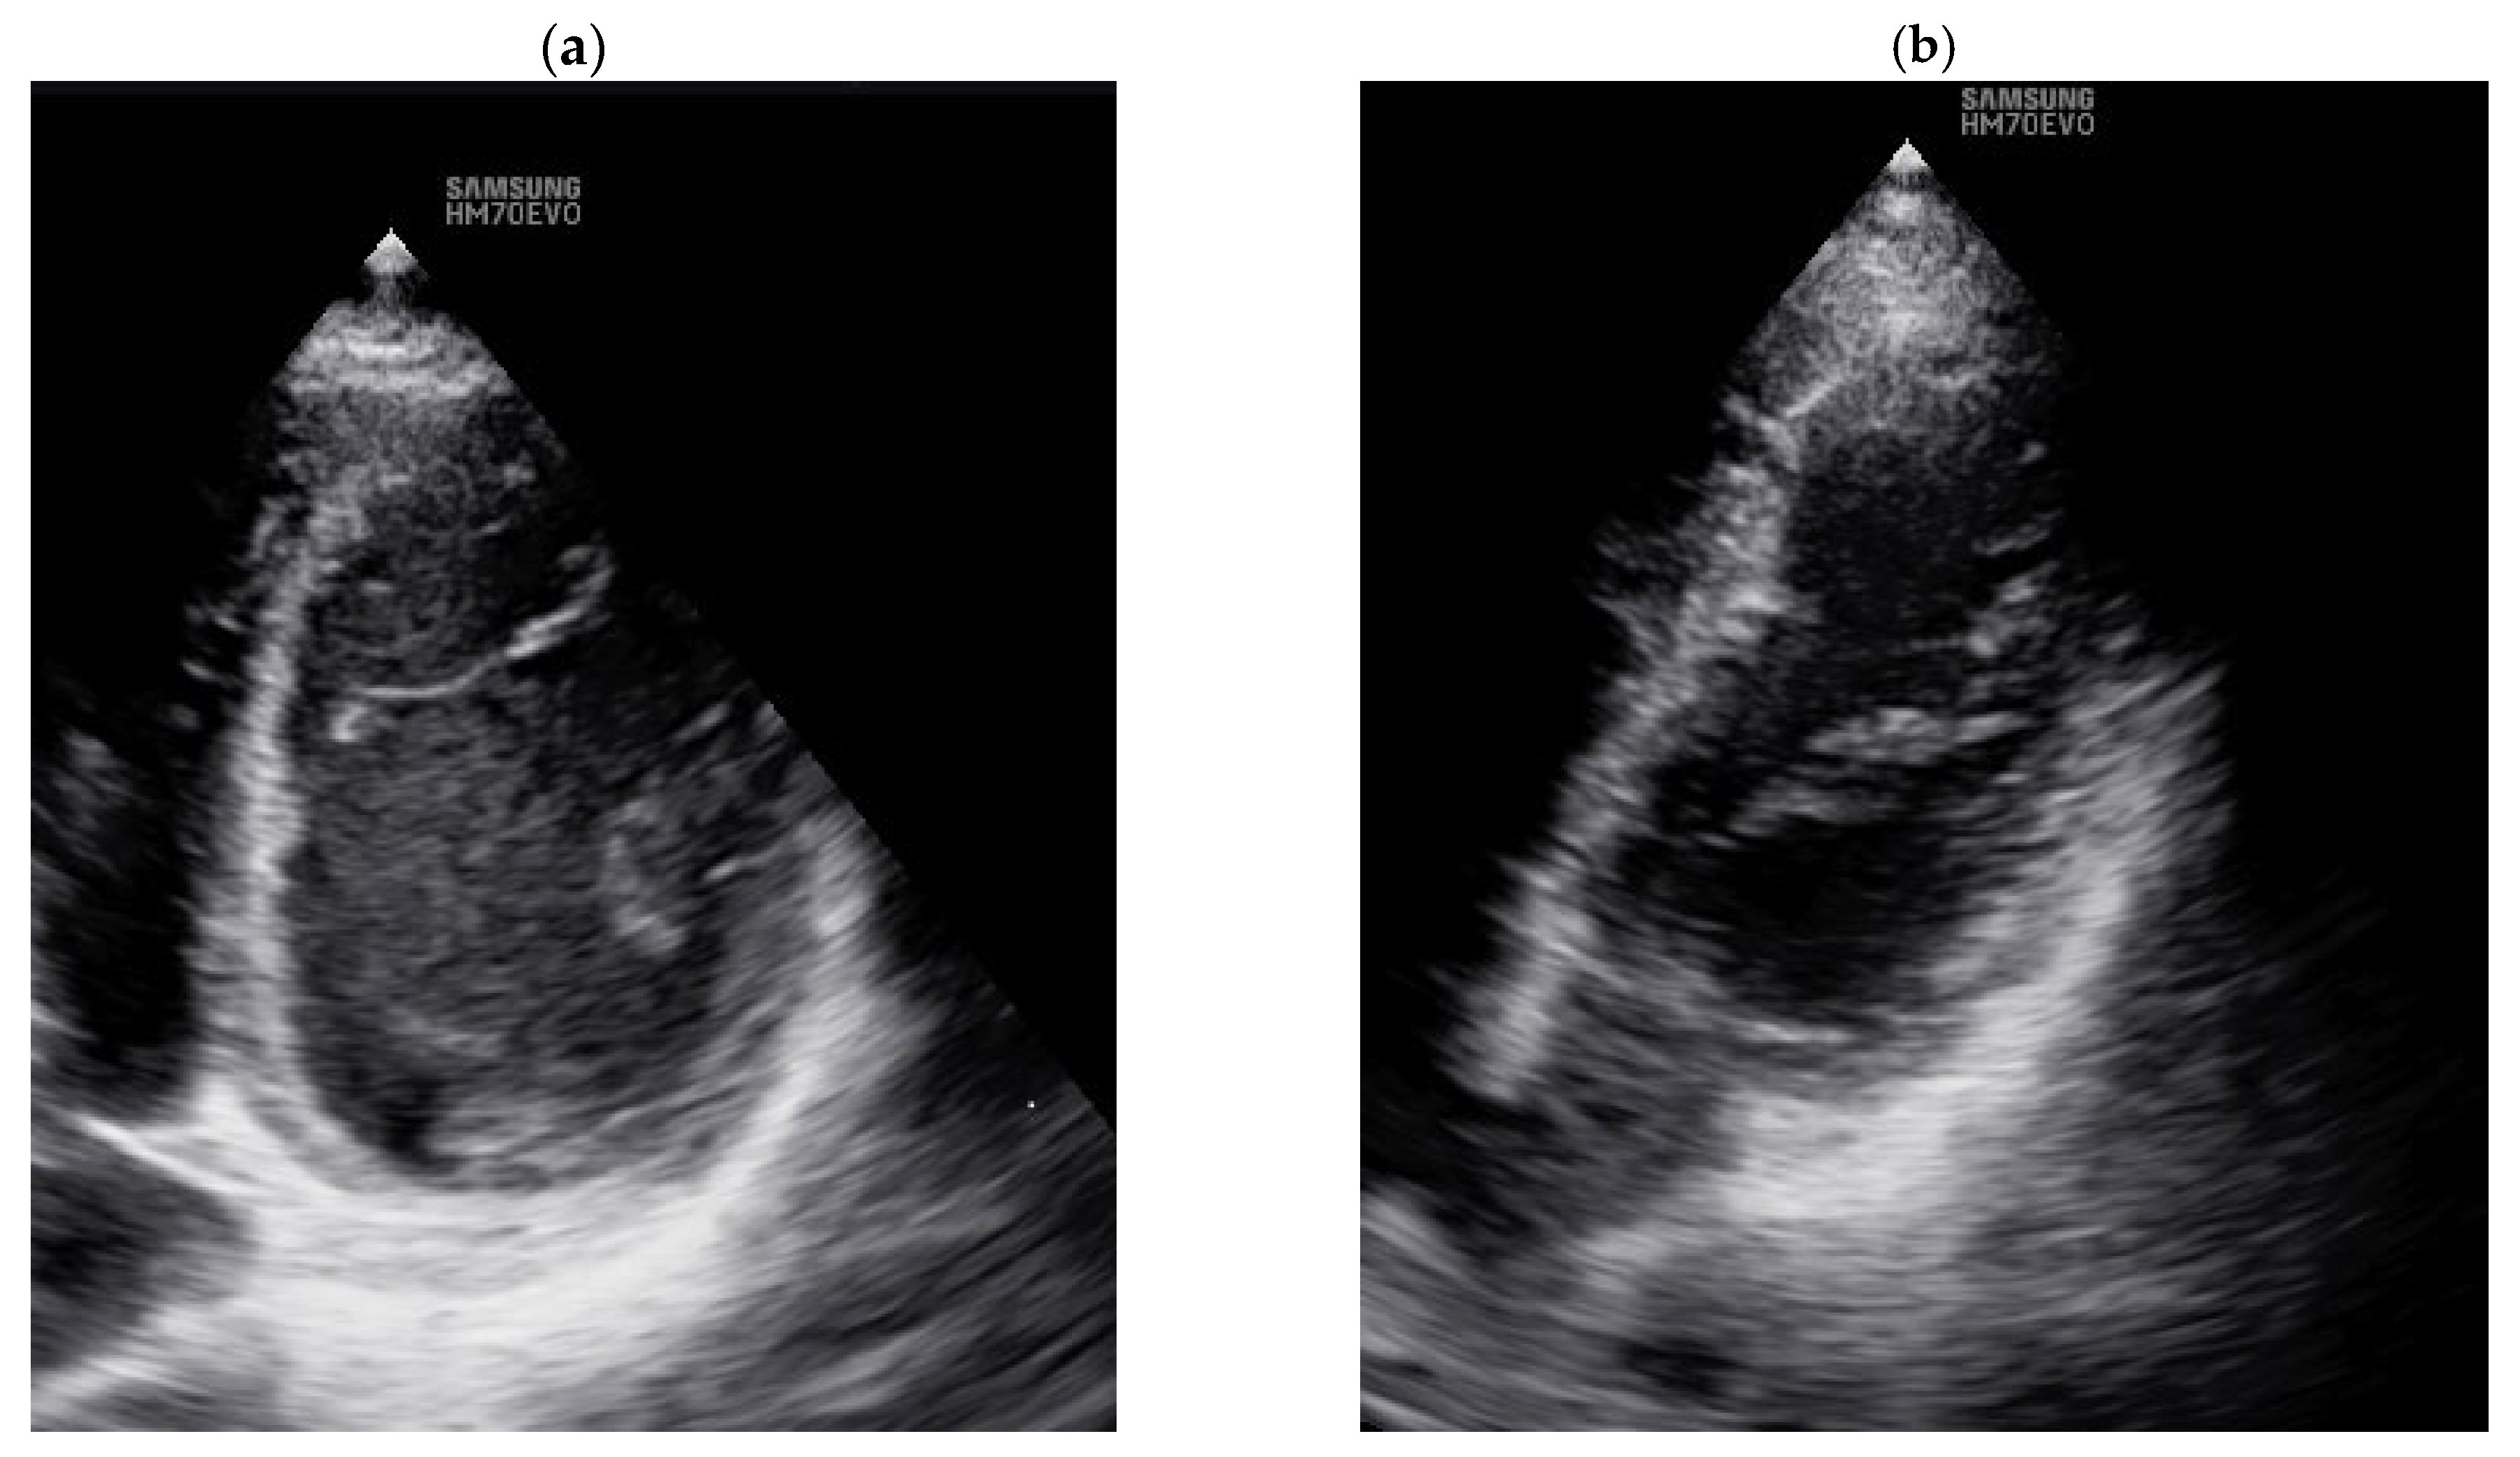

2.5. Transthoracic Echocardiography (TTE)

3.1. Echocardiographic Markers of CTD and TTE Data